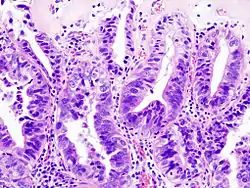

Gallbladder adenocarcinoma histopathology

Gallbladder carcinoma